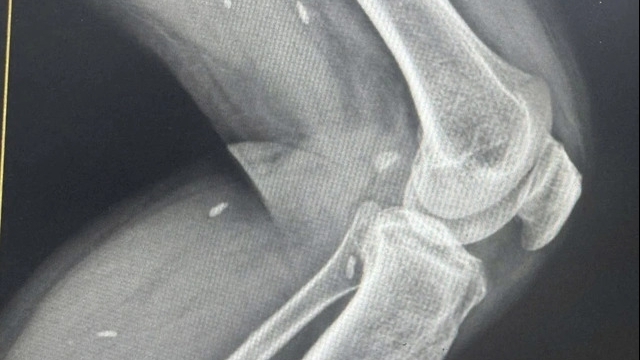

Tại thời điểm xảy ra cháy, có 15 phòng mổ đang phẫu thuật, 2 phòng mổ có bệnh nhân đang gây tê chuẩn bị phẫu thuật. Các phẫu thuật viên cố gắng nhanh nhất có thể hoàn tất các cá mổ và chuyển ra hồi sức. Có 1 ca phẫu thuật vẹo cột sống, thời gian kéo dài nên phải ngưng giữa chừng đóng vết mổ chuyển sang hồi sức.